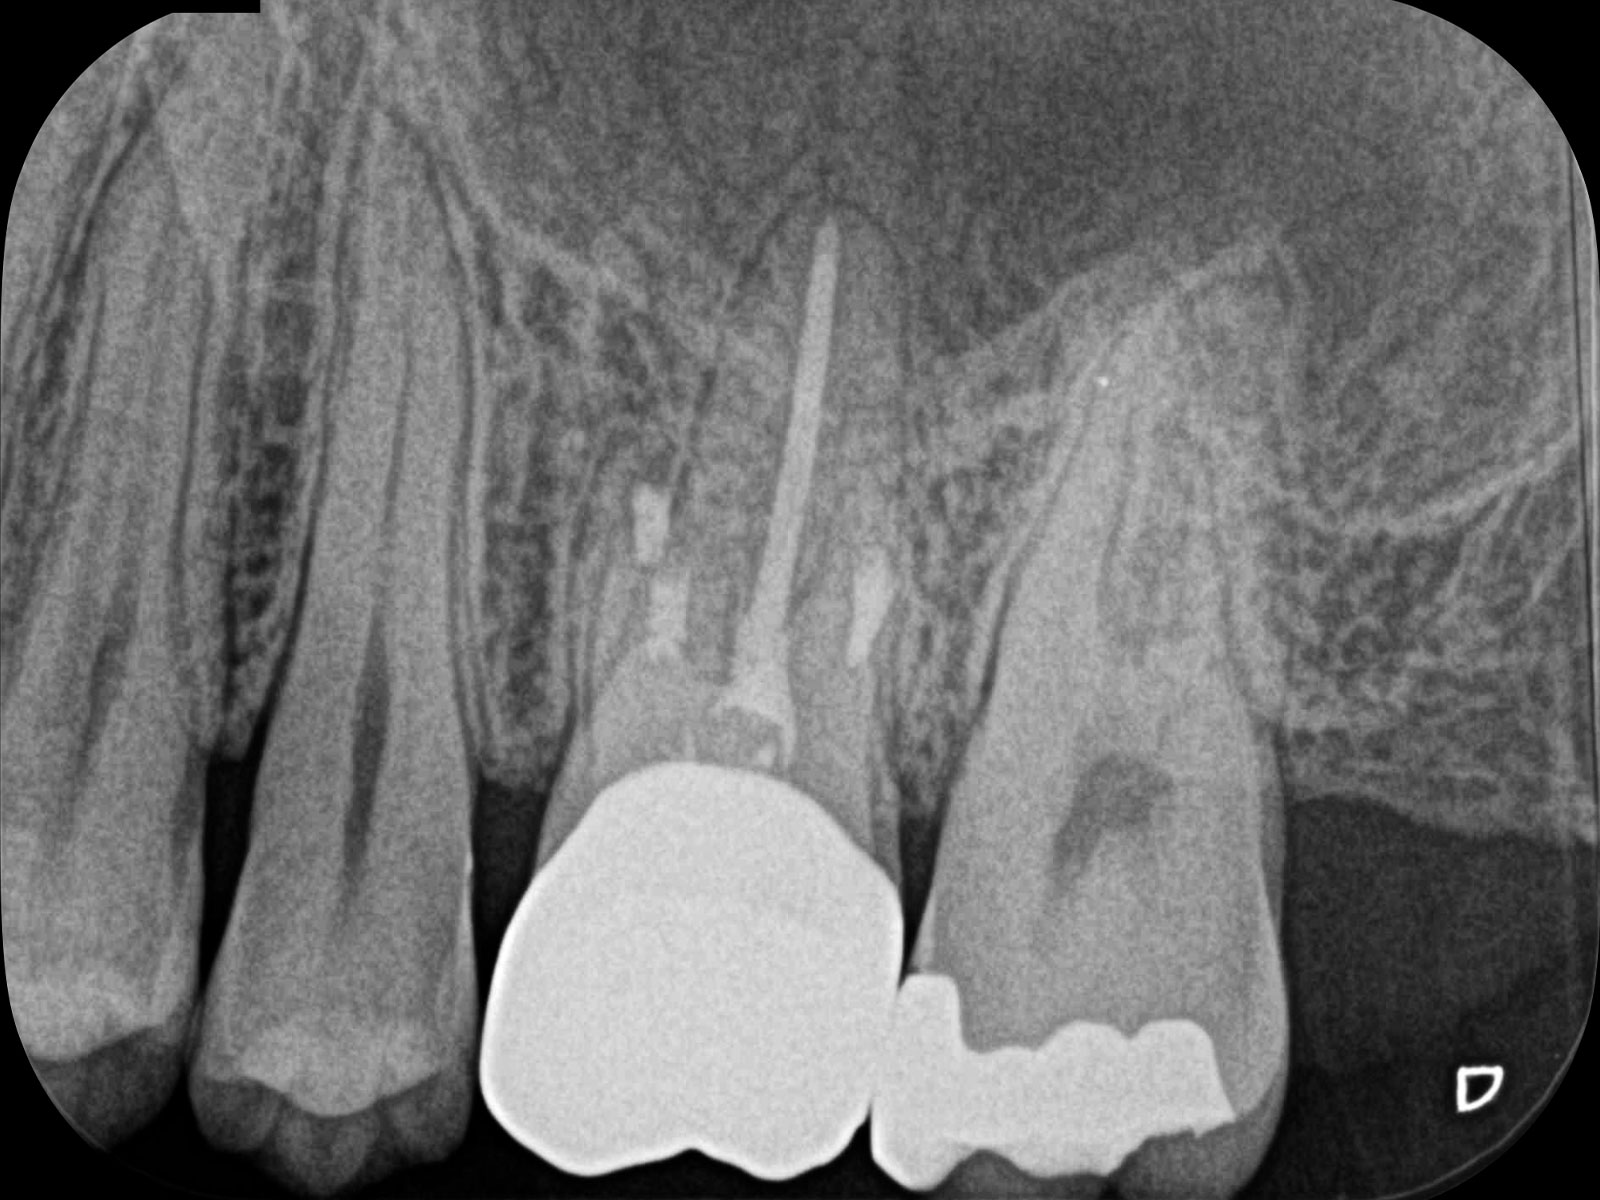

以下が実際に当院で処置した症例です。根管治療で痛みが再発する原因は、細菌が引き起こす炎症です。増殖した細菌が根の先まで進行し、膿がたまります(根尖病巣)。治療後は黒い影がなくなっていることがわかります。

「CT」は画像診断装置の一種です。3次元的(立体的)に治療部位を撮影できるため、血管や神経の位置関係など、通常のレントゲンでは得られない情報も得ることができます。

上記の画像は、CT(左)とレントゲン(右)の比較です。丸をつけている箇所が病巣なのですが、レントゲンだと発見できないことがおわかりいただけるかと思います。

根管を掃除する“細長いヤスリ”のような道具を「ファイル」といいます。

当院では「ステンレスファイル」を使用しています。このファイルは細くて硬い性質があり、歯根の先端までしっかり貫通させることができます。